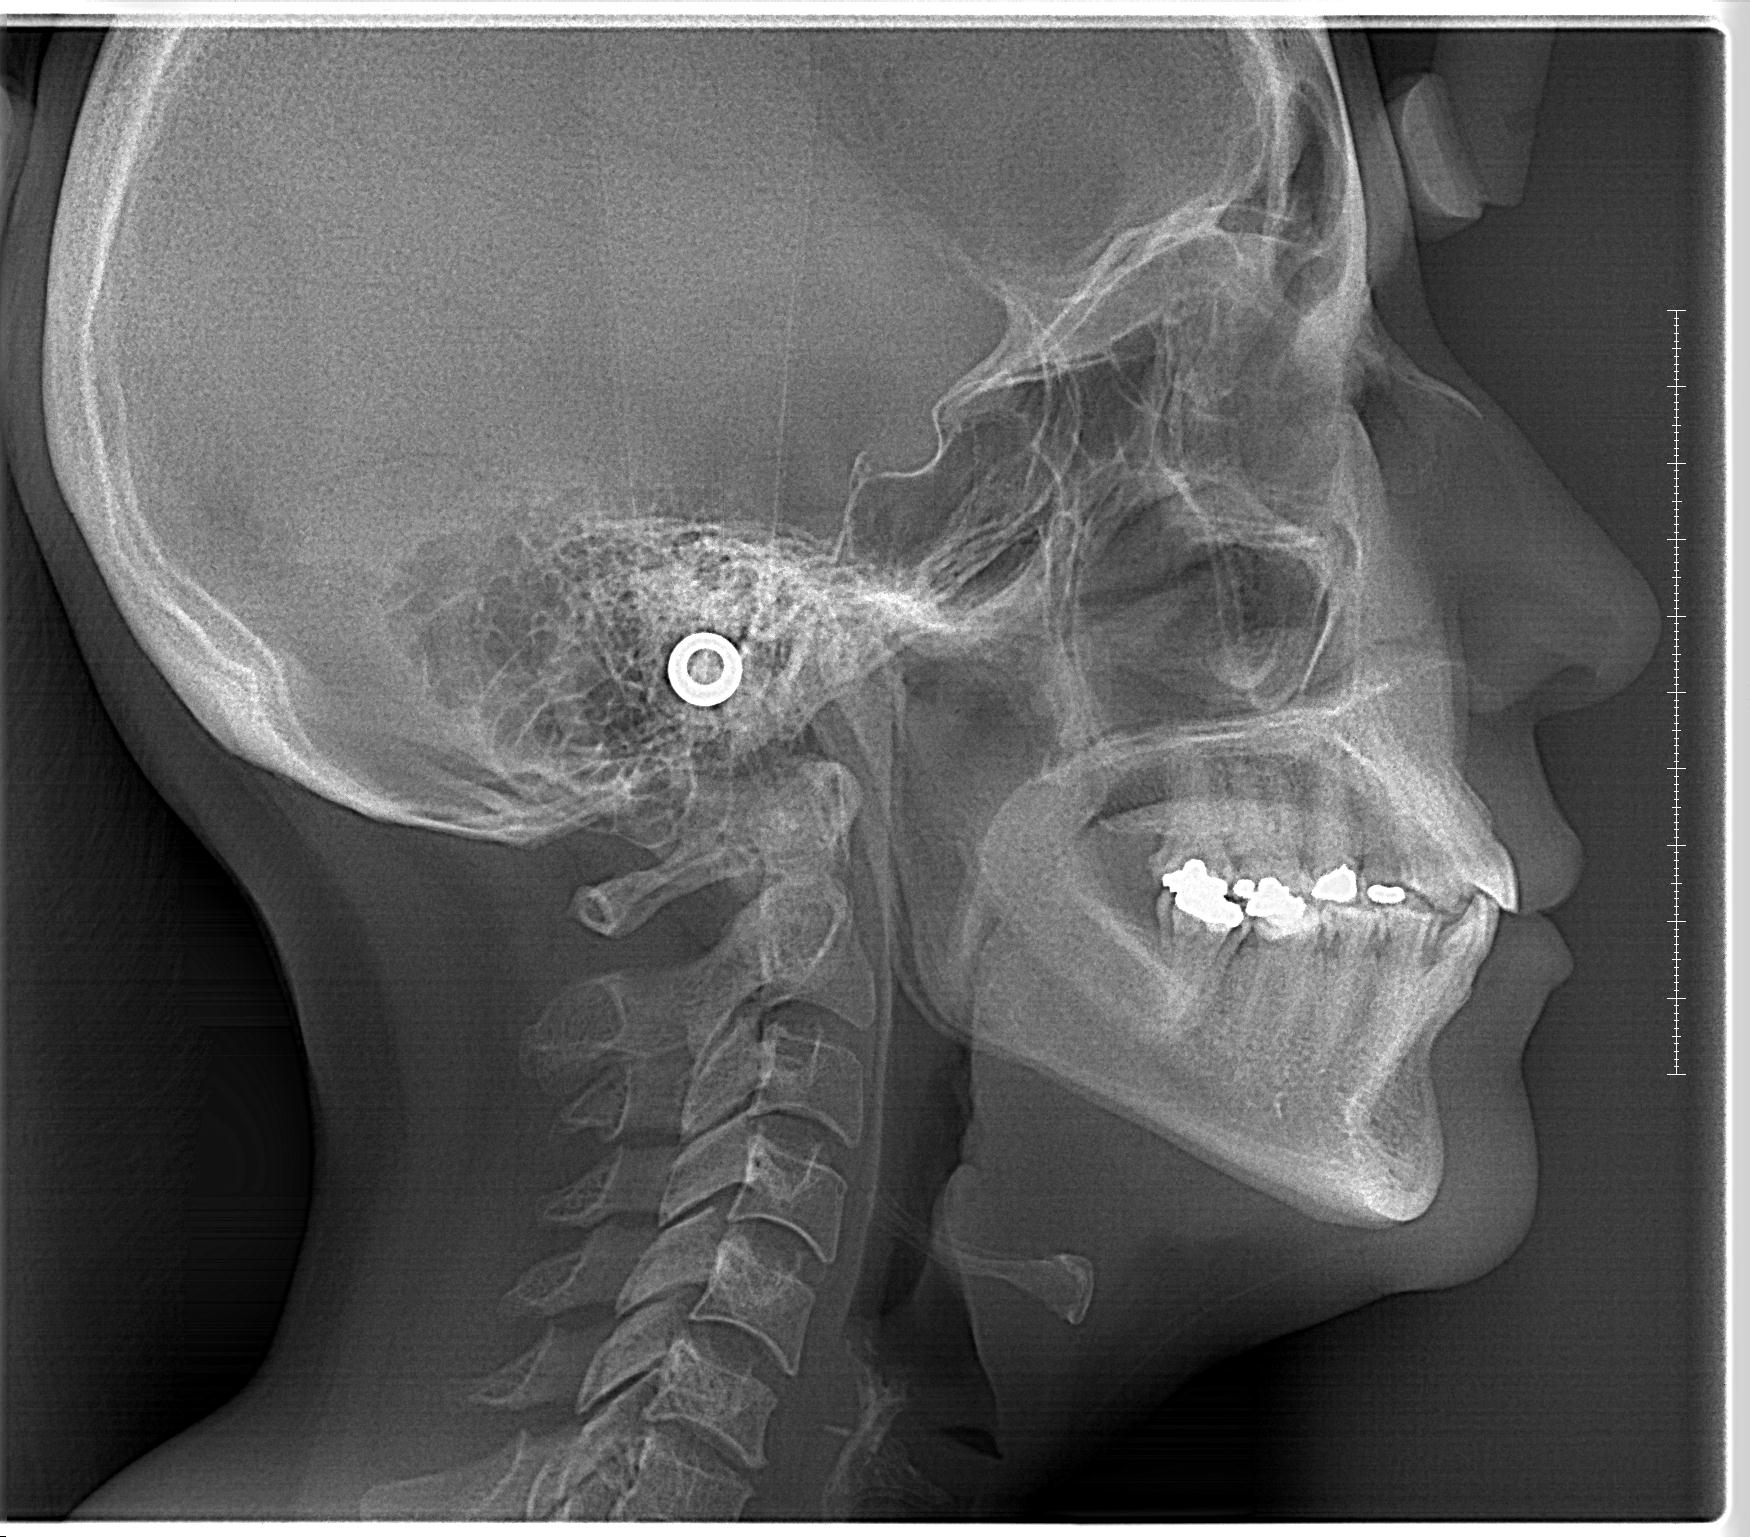

Rx Perfil

Radiografía muy útil para diagnosticar patologías craneomandibulocervicales y de mucha utilidad en ortodoncia.